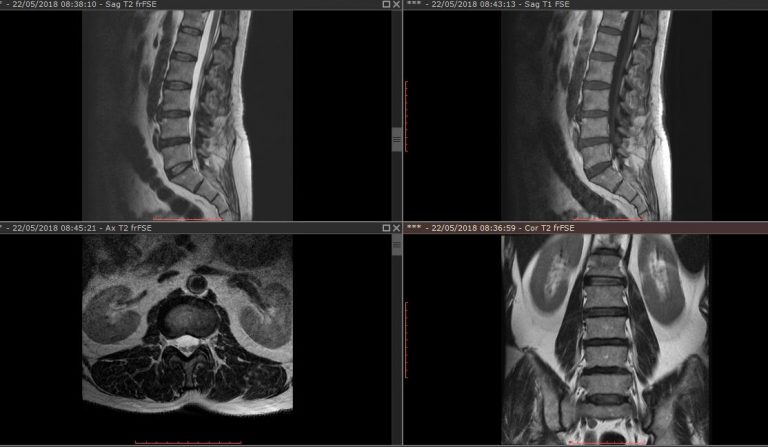

Cáncer de próstata en RM y PI-RADS

Avances en el diagnóstico del cáncer de próstata El cáncer de próstata es una patología muy frecuente en el ámbito clínico, siendo una de las neoplasias más frecuentes en hombres (la segunda neoplasia más frecuente en hombres en Estados Unidos en 2025 según cancer.org). Por lo tanto, son muchos los pacientes con esta patología, o…